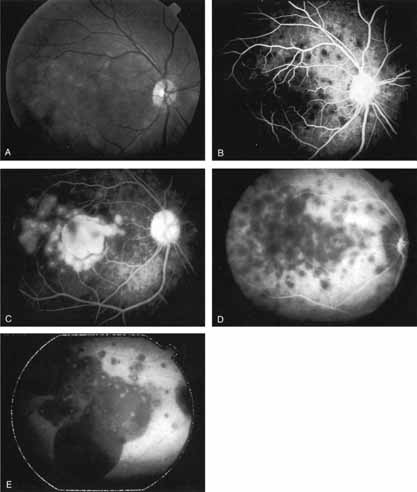

Harada disease, an inflammatory condition often affecting both eyes in young patients, is typified on fluorescein angiography by multiple focal areas of hypofluorescence early in the study, followed by late confluent leakage in the later phases (Fig. 17A, 17B, and 17C). With ICG angiography, multiple focal hypofluorescent spots are seen in the early phases, many more than were noted on the fluorescein study64,68 (Fig. 17D). The process extends further than the clinically or angiographically involved areas. The spots vary in size and density but appear to be well circumscribed. In the later phases of the ICG study, there is generalized hypofluorescence, with masking of the background choroidal fluorescence by the neurosensory detachment (Fig. 17E). This masking effect covers a large area, with inferior round margins confirming the gravitating nature of the neurosensory elevation. In addition, focal hyperfluorescent spots can be seen, possibly representing sites of active chorioretinal leakage or inflammation. In one patient, steroid therapy resulted in a marked resolution of clinical findings within 1 week.68 Repeat ICG angiography revealed a marked resolution of the hypofluorescent lesions as well as the hyperfluorescent spots. New areas of hypofluorescence did appear, the significance of which remains undetermined (Fig. 17E).

Fig. 17 Clinical photograph of a patient with Harada disease demonstrating multiple serous elevations of the retinal pigment epithelium with an overlying shallow neurosensory detachment. B. Early-phase fluorescein angiogram demonstrating hypofluorescent spots at the site of localized inflammation. C. Late-phase fluorescein study demonstrating hyperfluorescence in a confluent nature in the central macula. D. Early-phase indocyanine green (ICG) study demonstrating hypofluorescent spots in the central macular region. Note that the lesions are more numerous and more widely distributed than noted on clinical or fluorescein angiographic examination. E. Late-phase ICG study demonstrating extensive areas of confluent hypofluorescence. Note the curvilinear and gravitating nature of these hypofluorescent lesions, which are believed to represent blocked fluorescence from the shallow neurosensory detachment. Focal hyperfluorescent spots are noted within this region, which may represent areas of more active inflammation.